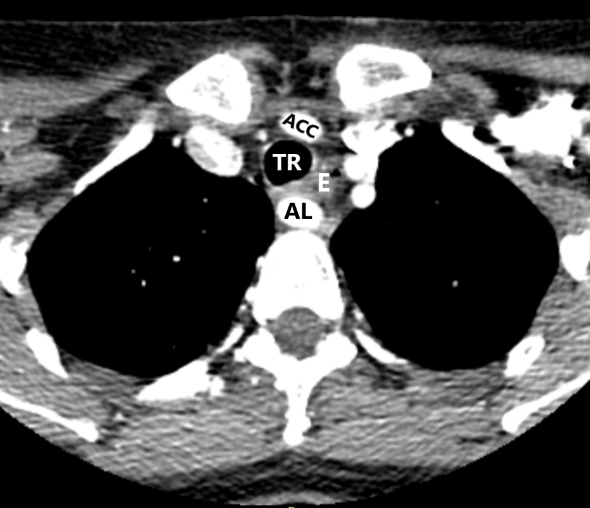

- На уровне правого грудино-ключичного сочленения AL и правая общая сонная артерия располагаются отдаленно друг от друга. Данная сонографическая картина выявлена у всех 4 пациенток (рис. 3).

- На уровне правого грудино-ключичного сочленения AL и правая общая сонная артерия располагаются перпендикулярно друг к другу. Данный признак выявлен у всех пациенток (рис. 4).

Рис. 2. Пациентка 32 лет, индекс массы тела (ИМТ) – 18,5. а – УЗИ сосудов верхнего средостения конвексным датчиком в В-режиме (цветное дуплексное сканирование менее информативно из-за множества помех от дуги аорты). Правая общая сонная артерия прослежена до дуги аорты (БЦС не выявлен). б – интраоперационная картина. НВГН IIA типа (по Avisse–Toniato) имеет горизонтальный ход. в – аксиальный КТ-скан с ангиографией сосудов дуги аорты. AL располагается позади трахеи и пищевода. г – компьютерная трехмерная реконструкция демонстрирует синтопию AL с общей сонной артерией. AL является последней, четвертой ветвью дуги аорты. ACC – arteria carotis communis dexter, TR – trachea, E – esophagus.

Рис. 3. Пациентка 58 лет, ИМТ – 21,7. а – цветное дуплексное сканирование сосудистого пучка правой половины шеи линейным датчиком на уровне правого грудино-ключичного сочленения. Правая общая сонная артерия прослежена до места “пересечения” с трахеей (БЦС не выявлен). AL располагается на значительном расстоянии от правой общей сонной артерии. б – интраоперационная картина. НВГН I типа (по Avisse–Toniato) имеет нисходящее направление и состоит из двух веток (стрелки). в – аксиальный КТ-скан с ангиографией сосудов дуги аорты. AL располагается позади трахеи и пищевода. г – компьютерная трехмерная реконструкция демонстрирует синтопию AL с общей сонной артерией. AL является последней, четвертой ветвью дуги аорты. ACC – arteria carotis communis dexter, TR – trachea, E – esophagus. VJI – vena jugularis interna dexter, NV – nervus vagus dexter.

Рис. 4. Пациентка 68 лет, ИМТ – 31,6. а – УЗИ сосудистого пучка правой половины шеи линейным датчиком в В-режиме. б – цветное дуплексное сканирование сосудистого пучка правой половины шеи линейным датчиком. AL расположена параллельно плоскости сканирования. Правая общая сонная артерия и трахея находятся перпендикулярно относительно датчика. в – интраоперационная картина. Мобилизована правая доля ЩЖ, отведена медиально. НВГН состоит из двух веток (стрелки). г – интраоперационная картина. Выполнена тиреоидэктомия. НВГН IIA типа (по Avisse–Toniato) имеет горизонтальный ход. д – аксиальный КТ-скан с ангиографией сосудов дуги аорты. AL располагается позади трахеи и пищевода. е – компьютерная трехмерная реконструкция демонстрирует синтопию AL с общей сонной артерией. AL является последней, четвертой ветвью дуги аорты. ACC – arteria carotis communis dexter, TR – trachea, E – esophagus.